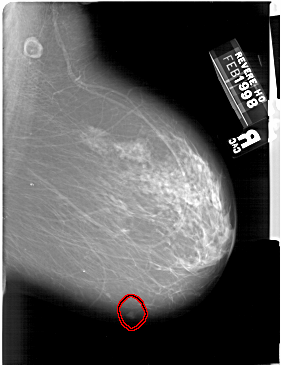

A_1539_1.RIGHT_CC

RIGHT_CC LINES 6796 PIXELS_PER_LINE 4561 BITS_PER_PIXEL 12 RESOLUTION 43.5 OVERLAY

FILE: A_1539_1.RIGHT_CC.OVERLAY

TOTAL_ABNORMALITIES 1

ABNORMALITY 1

LESION_TYPE MASS SHAPE LOBULATED MARGINS ILL_DEFINED

ASSESSMENT 4

SUBTLETY 4

PATHOLOGY MALIGNANT

TOTAL_OUTLINES 1

BOUNDARY